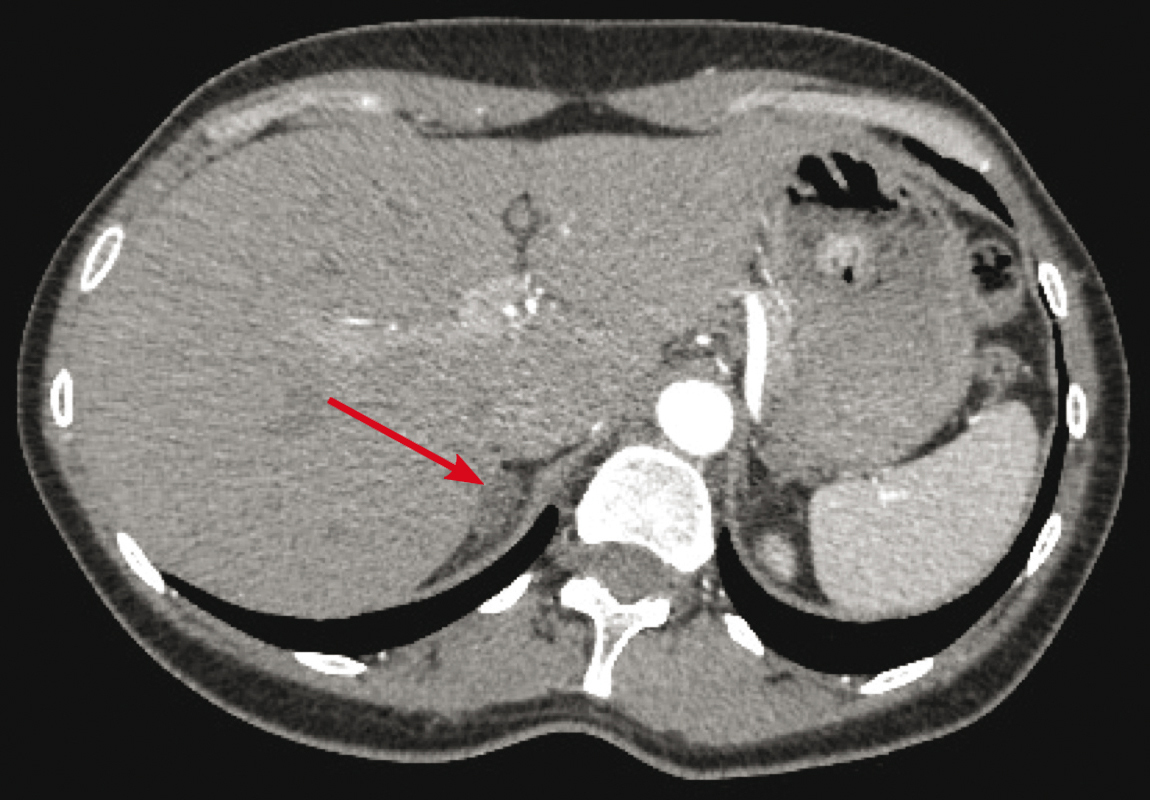

Il s'agit de l'aspect tomodensitométrique d'un adénome producteur d'aldostérone avec nodule surrénal droit de 17 mm de grand axe et de densité de 4 unités Hounsfield (UH). Une fois le diagnostic hormonal d'hyperaldostéronisme primaire confirmé, une imagerie des surrénales est réalisée, le plus souvent par tomodensitométrie (TDM). L'objectif est double :

– éliminer une tumeur maligne par la taille (un cortico-surrénalome mesure généralement plus de 4 cm) et la densité avant injection (une lésion < 10 unités Hounsfield est un adénome dans 98 % des cas) ;

– rechercher un adénome producteur d'aldostérone typique, décrit comme un nodule surrénal unique, de 10 à 20 mm de grand axe, sans lésion de la surrénale controlatérale comme ici. La TDM suggère mais ne permet pas d'affirmer la présence d'un hyperaldostéronisme primaire unilatéral. Les incidentalomes de petite taille sont en effet fréquents et peuvent être associés à une hyperplasie bilatérale. Plusieurs études ont montré que si la décision de surrénalectomie n'était prise que sur la TDM, 20 % des patients ayant un hyperaldostéronisme primaire latéralisé n'auraient pas été opérés et la chirurgie aurait été proposée à 25 % des patients ayant un hyperaldostéronisme primaire bilatéral. La fréquence des incidentalomes augmente avec l'âge ; <em>a contrario,</em> on estime qu'avant 35 ans un hyperaldostéronisme primaire associé à un nodule surrénal unique est un adénome producteur d'aldostérone.